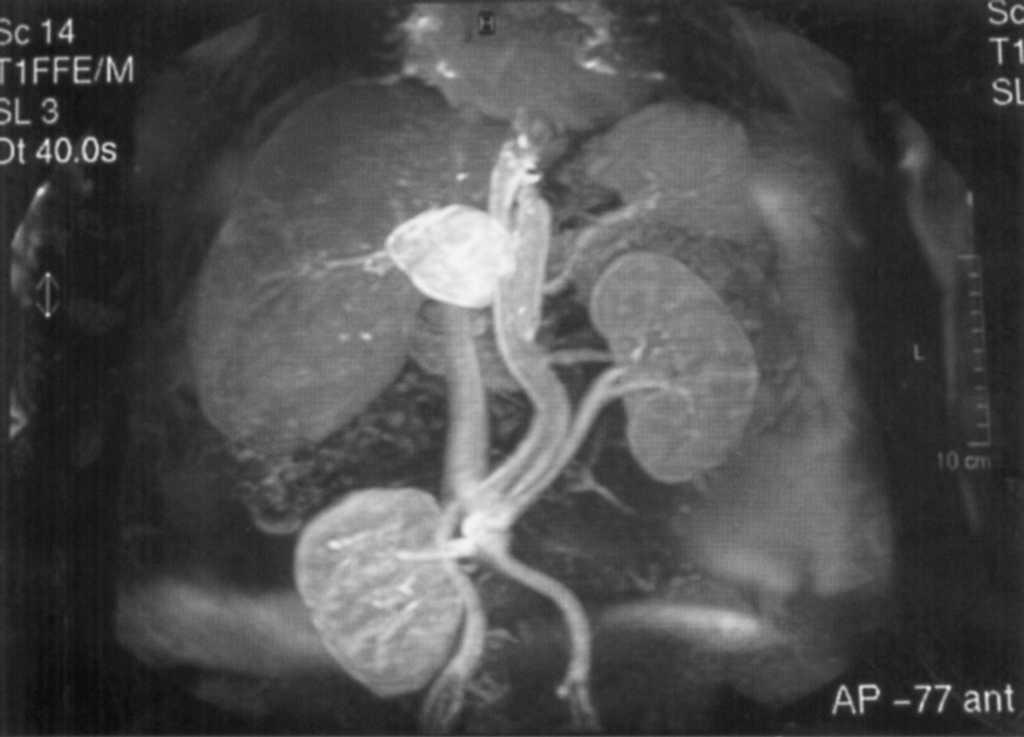

En la ecografía abdominal se aprecia dilatación ligera de colédoco (10,2 mm) y vías biliares intrahepáticas, así como esteatosis hepática sin lesiones ocupantes. La resonancia magnética y la colangiorresonancia descartan alteraciones de la via biliar; sin embargo, se comprueba un aneurisma de 7 cm de diámetro en la arteria hepática (figs. 1 y 2).

Fig. 1. Angiorresonancia que muestra el aneurisma que afecta a toda la arteria hepática común.